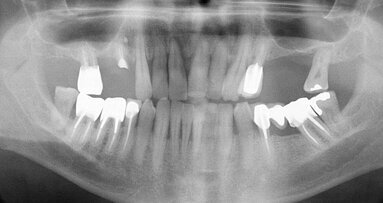

Examen clinique et radiologique L’examen clinique et radiographique met en évidence la possibilité de poser un implant (Figs. 1 et 2).

Fig. 1 : Radio panoramique, on visualise bien le secteur édenté en 46.